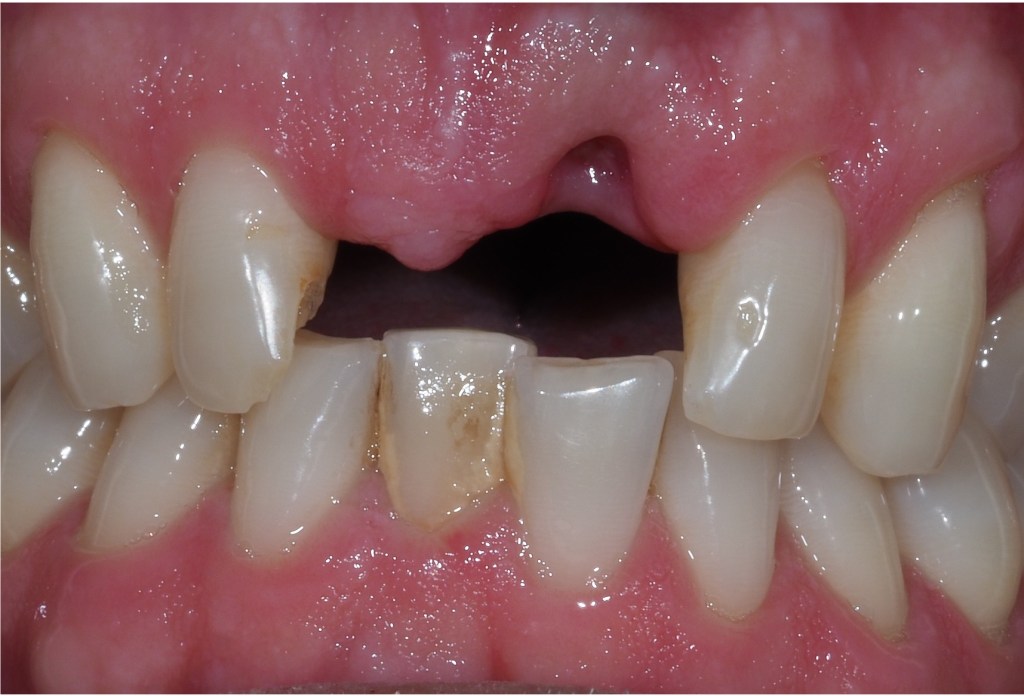

Single implant crowns are an excellent way to replace missing teeth. They do not damage the neighbouring teeth and last for a long period of time. These are usually screw retained to allow repair/replacement if there are any maintenance issues.